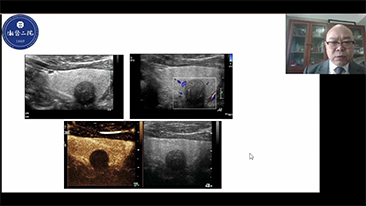

How Clearly Can You See a Liver?

Ultrasound contrast imaging plays a significant role in identifying focal liver lesions, such as hemangioma or liver cancer.

Ultra-wide non-linear UWN+ contrast imaging technology provides better penetration, higher contrast-tissue ratio, with lower MI and longer perfusion time observation.